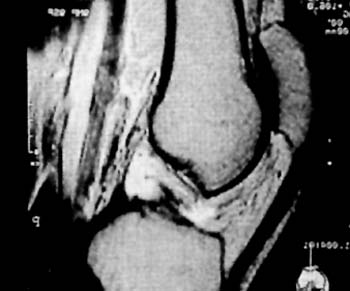

Los estudios Rx, y de TAC fueron en todos los casos negativos, en cambio, se destaca la RNM como metodo fundamental para su diagnostico. (Fig 1)

El mismo se caracteriza por su ubicacion central adosado al Ligamento Cruzado Posterior desplazando hacia lateral al Ligamento Cruzado Anterior.

Su densidad lo asemeja como un tumor con caracteristicas liquidas y su forma multilobulada ocupa practicamente el intercondilo femoral (Fig 2-3-4) En T2 es facilmente distinguible como una masa homogenea que ocupa todo el contorno del condilo femoral interno.

Figura 2